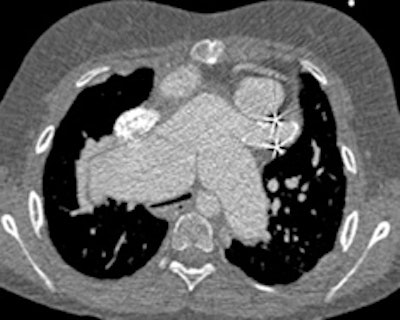

Same 14-year-old patient, there is mark dilatation of the pulmonary tree, causing compression of the trachea at the carina (top) and on the left main bronchus behind the aneurysmal right pulmonary artery (bottom)